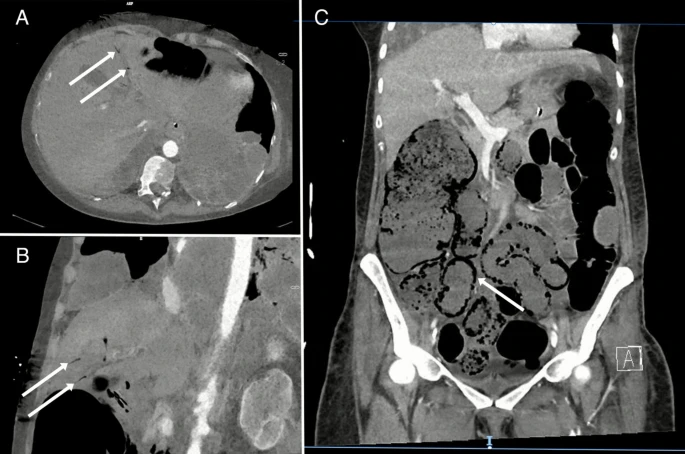

Abdominal computed tomography (CT) confirmed the presence of portal venous gas and pneumatosis intestinalis in the ileum and ascending colon, with patent mesenteric arteries (Fig. 1, panel A, B and C respectively). Non-occlusive mesenteric ischemia (NOMI) was diagnosed and partial bowel resection was performed. In pneumatosis intestinalis, disrupted mucosa and increased intraluminal pressure allow luminal air to enter capillary veins, draining into the portal vein. Although diagnosing intestinal ischemia in sedated and neuromuscularly relaxed patients can be challenging, the identification of portal venous gas via point-of-care ultrasound by intensive care physicians facilitates prompt diagnosis.